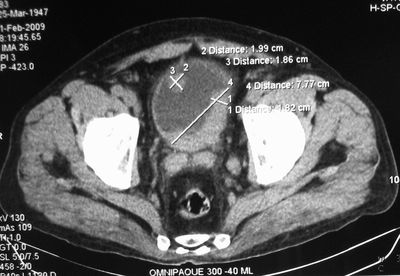

Опухоль мочевого пузыря